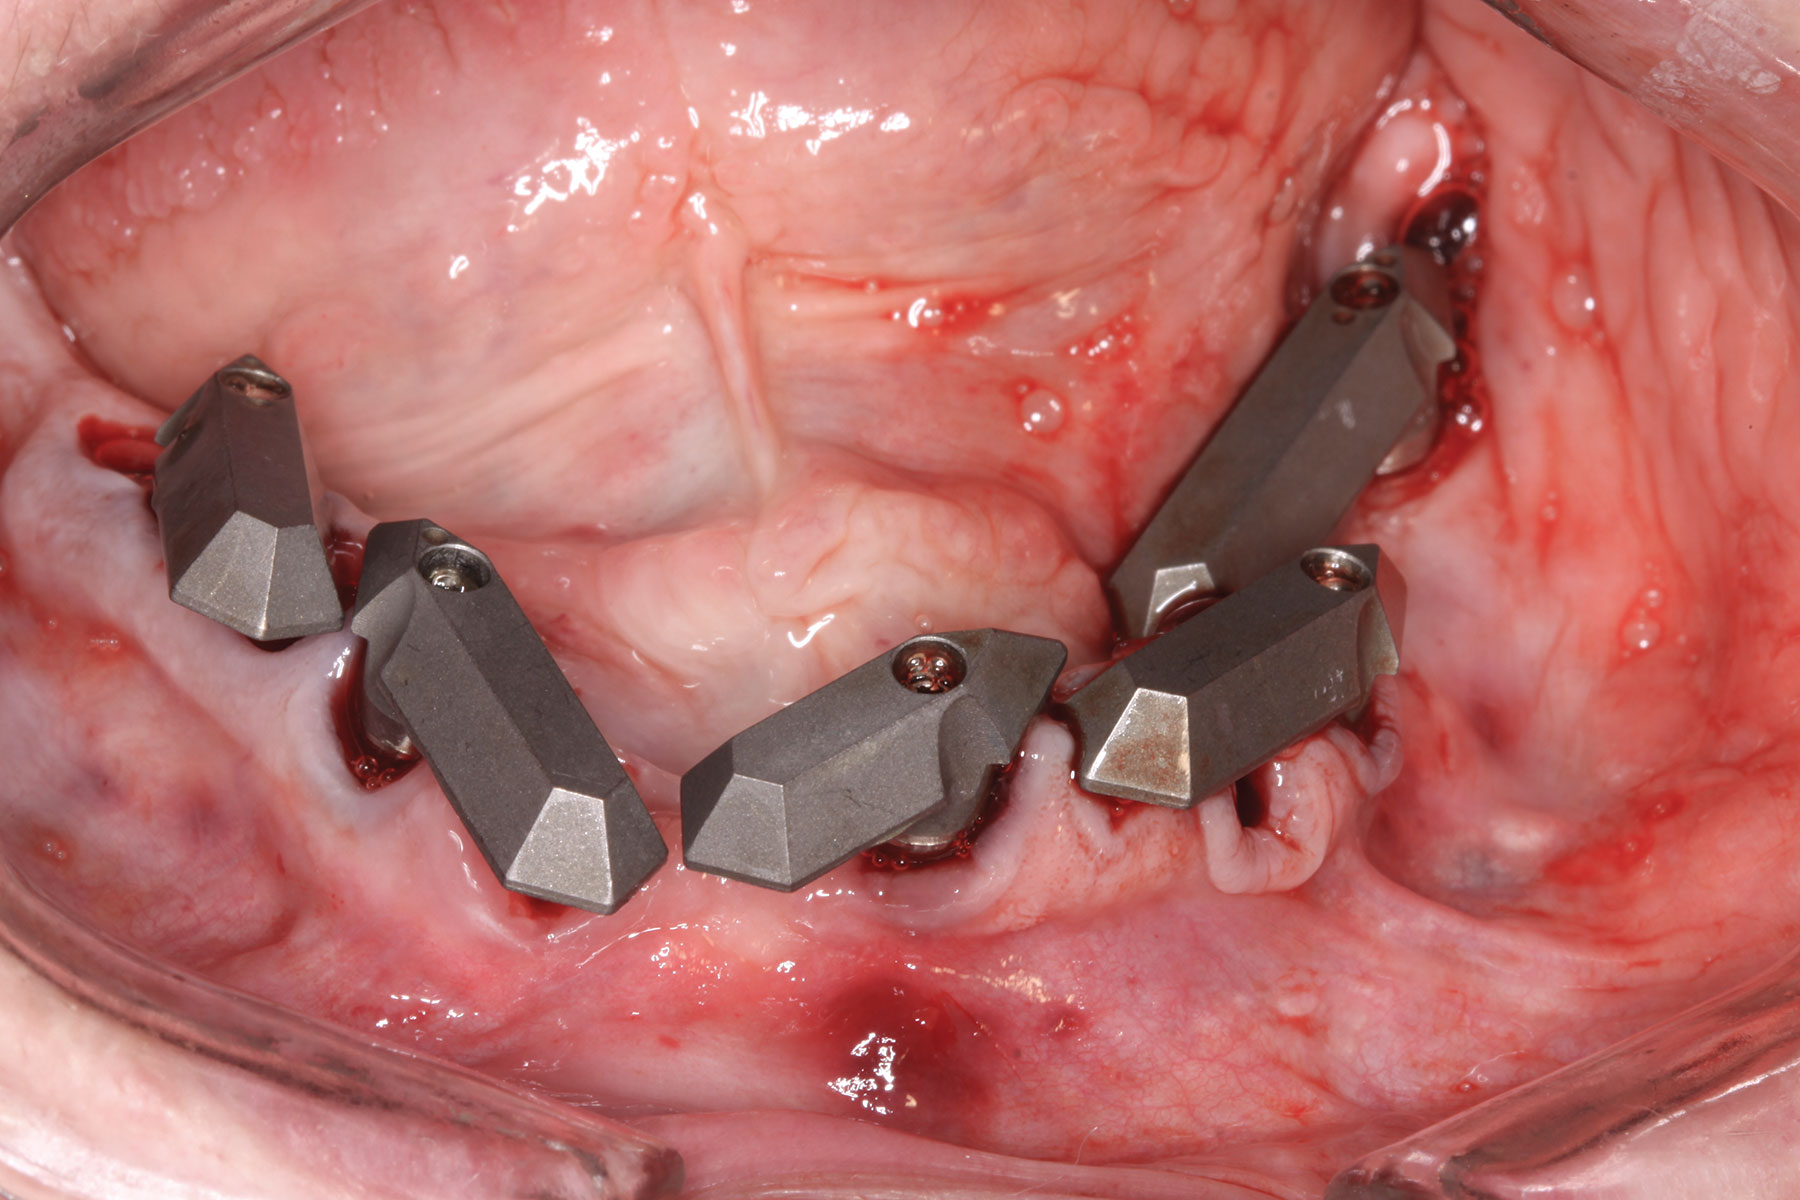

At the next visit, the patient was anesthetized with xylocaine with 1:100,000 epinephrine. Teeth Nos. 22, 27, and 28 were retained and all other mandibular teeth were extracted. Immediate implants were placed in prosthetically correct positions and multi-unit abutments were torqued to 30 Ncm. This was followed by insertion of screw-retained scan gauges in positions Nos. 18, 24, and 30.

Fig 29. Mandibular flapless immediate implant surgery completed and multi-unit abutments secured to implants.

Figure 29

Fig 30. All mandibular scan gauges in place.

Figure 30